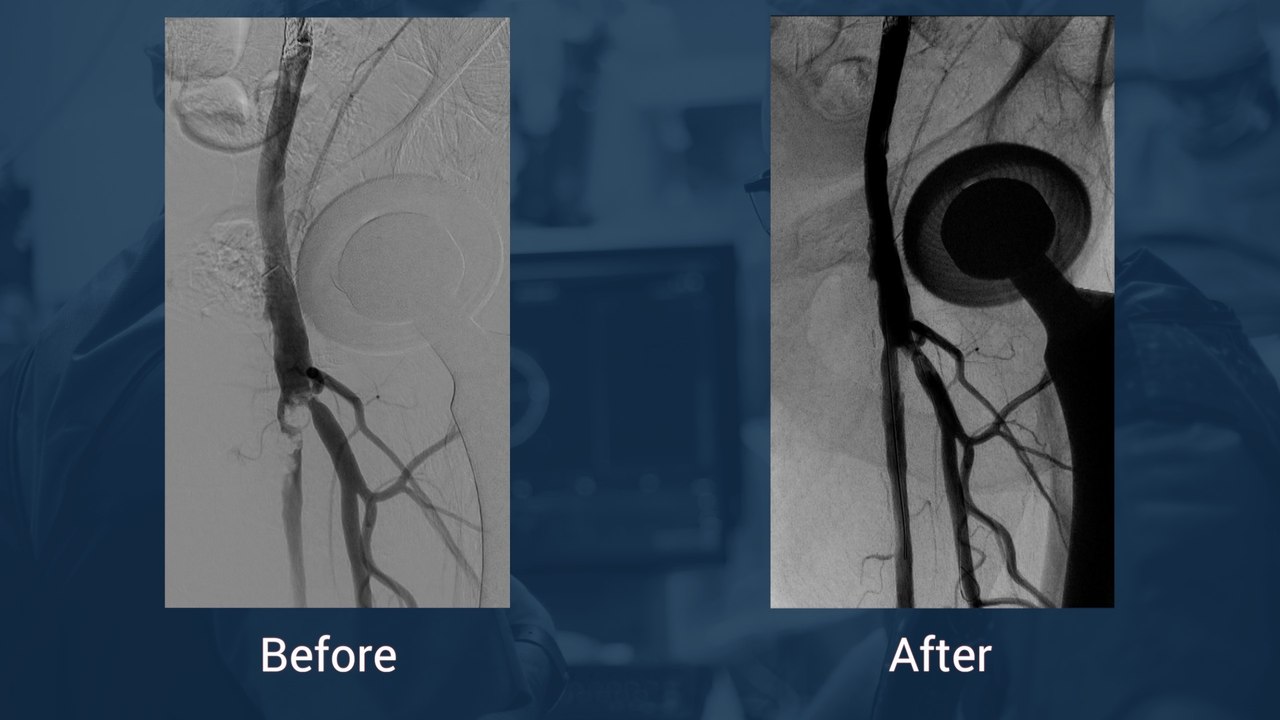

Tortuous and calcified ostial RCA CTO